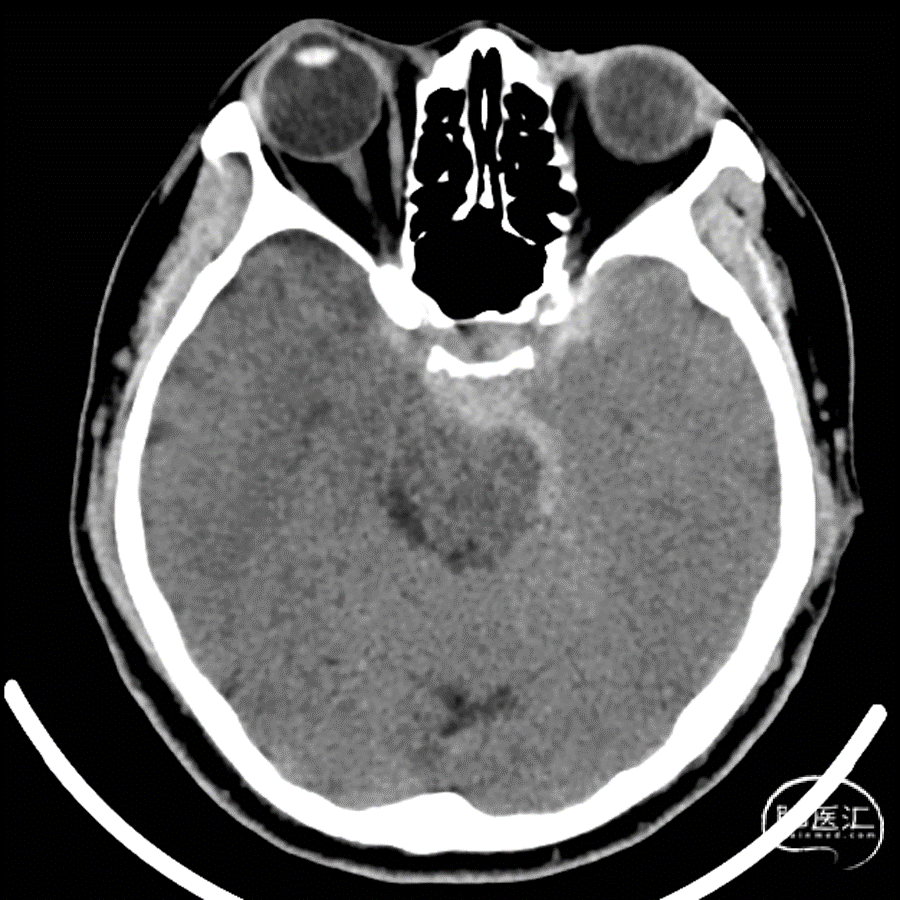

现病史:3小时前突发头痛,急诊行头颅CT提示:自发性蛛网膜下腔出血

头颅CT